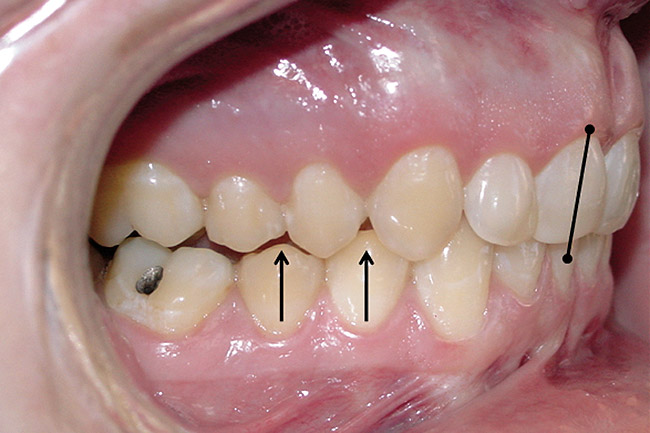

The position, shape, length, and inclination of the maxillary canines will affect the anterior frenal midline position of the mandible. This position may or may not coincide with the midline of the teeth, but gives an indication of the location of the left and right condyles in their fossae. The canines serve as lateral positioners of the mandible. The more lingual the maxillary canine inclination on one side, the more the mandible will shift to the opposite side and the condyle distalize on the opposite side (Figure 6, Figure 7 and Figure 8).

Figure 6  The inclination of the canines provide  the midline position of the mandible. When these  teeth are inclined (eg, the right canine in this  case), they tend to shift the mandible away from  the midline (in this case toward the left).

Figure 6

Figure 7  The left side of the patient shows how  maxillary molars and premolars can cause the  mandibular molars to be lingually inclined as  the teeth come into occlusion.

Figure 7

Figure 8  This case shows the shift of the  mandible from the point of first contact to full  closure because of the anterior restriction, which  has caused the mandible to shift posteriorly and  to the left. This patient experienced symptoms  of right lateral pterygoid tenderness with left  TMJ pain, left-sided headaches, and neck stiffness.  Release of this restriction allowed the  mandible to reposition itself to the midline with  reduction of the symptoms.

Figure 8